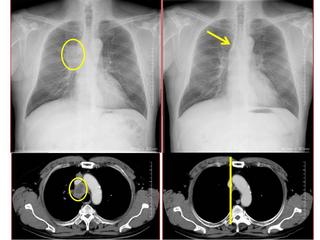

CTで見ると…

3Dだと、こうなります。

気管狭窄ですね。こういう所見もレントゲンで捉えることができるのです。